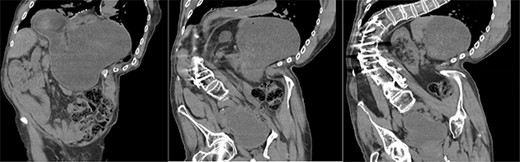

A 67-year-old man presented to the emergency department with sudden onset epigastric abdominal pain and vomiting, on a background of a known hiatus hernia awaiting surgical management. The patient continued passing flatus but was not able to tolerate any per oral fluid intake, vomiting any intake that was attempted. Medical history was relevant for severe KS, spina bifida, reflux, recurrent urinary tract infection, and an anterior approach spinal fusion surgery. Examination was significant for severe KS, with a soft and non-tender abdominal examination. Biochemically, the patient had a very mildly raised white cell count of 12.6 † 109/l. A CT of the abdomen and pelvis was obtained that identified the progression of a known hiatus hernia in comparison with an earlier CT, containing the distal portion of the stomach. The CT showed a distended and fluid filled oesophagus and stomach, along with fat stranding around the distal stomach, concerning for obstruction and possible strangulation of the moderate hiatus hernia, along with the known severe KS (see Figs 1 and 2). A nasogastric tube was placed to decompress the stomach (see Fig. 3). Following discussion with the patient regarding their current presentation and risks of operative management, laparoscopic hiatus hernia repair and fundoplication was undertaken, which was uncomplicated, although the dissection was difficult secondary to the severe scoliosis. Intra-operatively, it was noted that the hernial sac contained a grossly dilated stomach, with all hernial contents assessed as being viable, with nil signs of ischaemia. The peritoneal sac was not resected and left in situ, with a four-stitch horizontal posterior cruroplasty undertaken, along with a 180-degree anterior fundoplication. There was concern that recovery may be complicated by respiratory failure due to the severe KS; however, the patient had no respiratory compromise, begun passing flatus, opened his bowels, and tolerated a puree diet in the days following the operation. At post-operative clinic review 4 months following the hiatus hernia repair, the patient was well, described nil issues, and was tolerating a full diet.

Coronal slices of CT scan showing a moderate hiatus hernia with concern for obstruction and strangulation, with severe kyphoscoliosis.